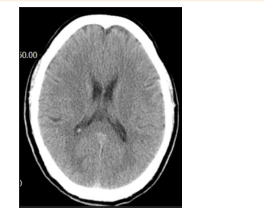

急诊心电图:未见明显异常。头颅CT:如图。

(3)头颅CT未见明显异常,可排除脑出血。(0.5分)